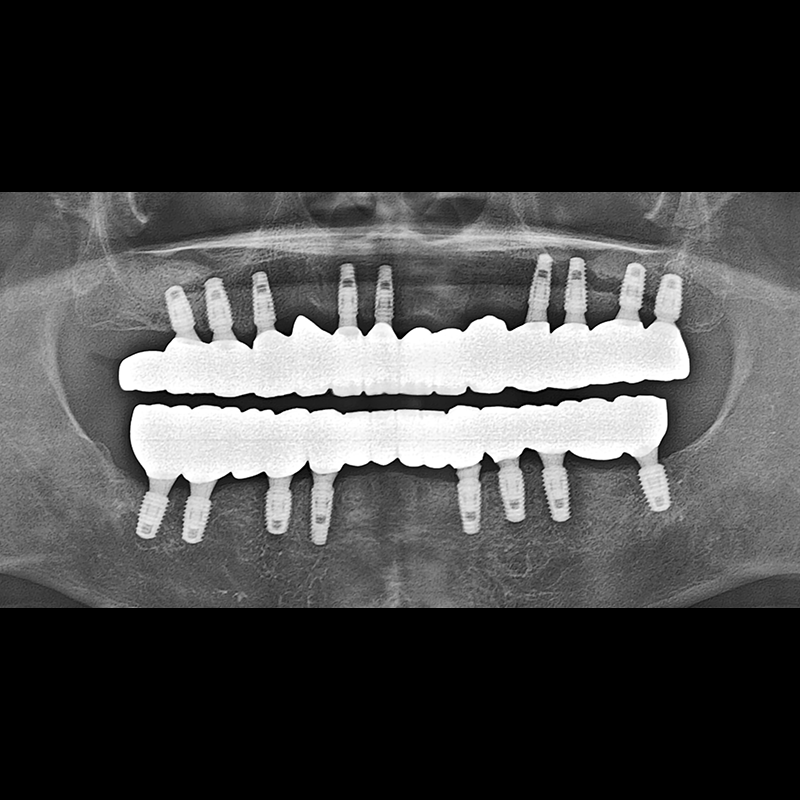

BEFORE AFTER

种植牙前后的照片 2025.05.30

在缺失的牙齿部分和难以挽救的牙齿位置植入了种植牙。